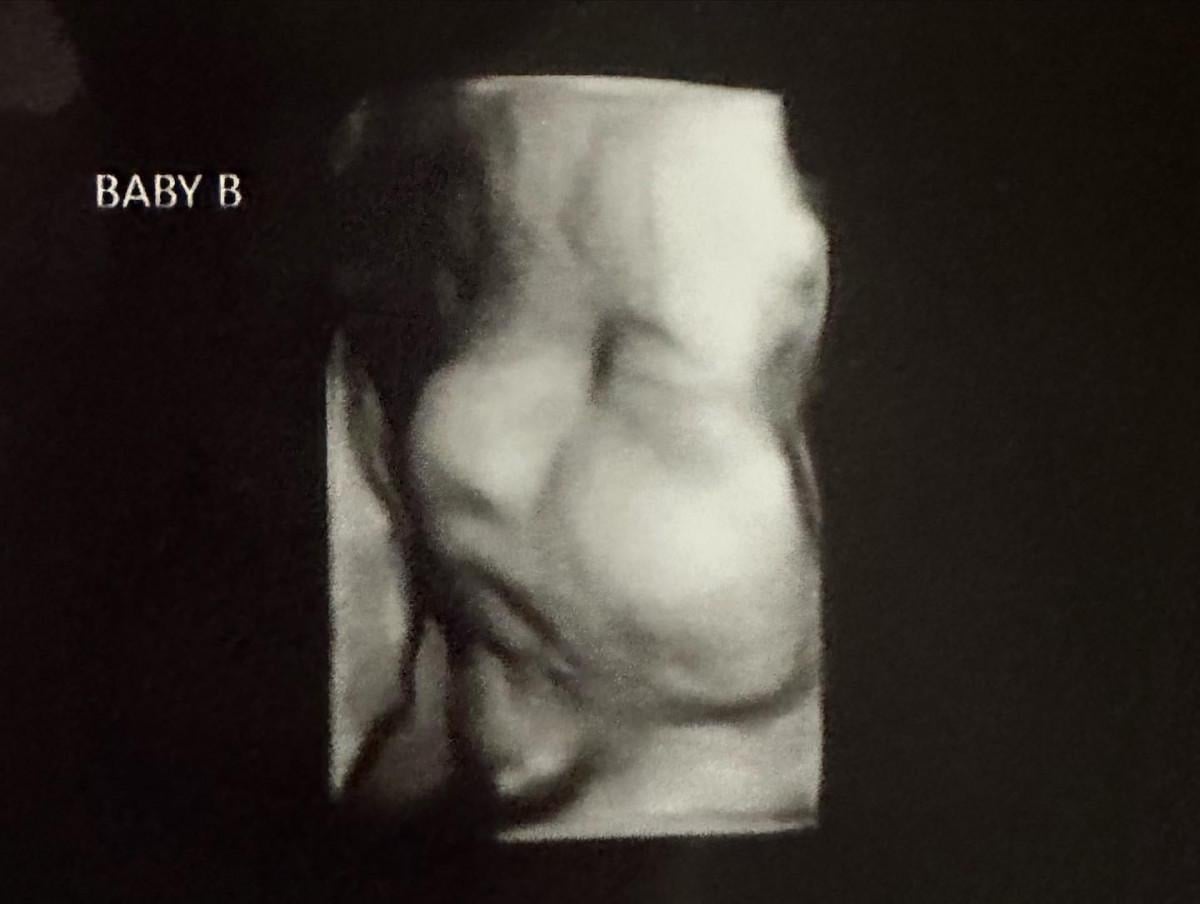

Kelsey Hatcher isimli bir kadın, doğuştan çift rahmi olduğunu ve nadir görülen bir hamilelikle her iki rahminde de kız bebek beklediğini duyurdu.

Hatcher'ın doktoru, genç kadının iki rahminde iki ayrı bebeğe aynı anda hamile kalmasının milyonda bir olduğunu ifade etti.

ABD’nin Alabama eyaletinde yaşayan 32 yaşında, üç çocuk annesi Kelsey Hatcher, uterus didelphys veya iki uterus adı verilen nadir bir uterus anomalisiyle doğdu.

Önceki hamileliklerinde sadece tek bir rahminde bebek taşıyan Hatcher, bebeklerin ikiz mi olacağı konusunda henüz bir bilgi veremediklerini söyledi.